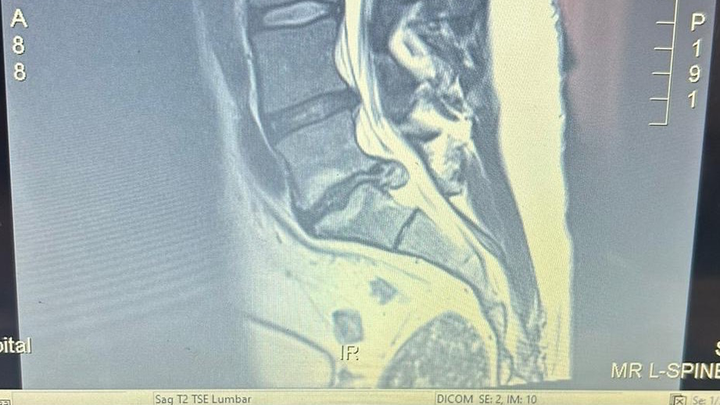

Hey. JoVan is going to Mexico for back surgery. For his back. His sore back. LC1 or 5 or 3 is in bad shape and cartilage or cartage or coralage is shot. Pinched nerve maybe? Hence he has a back that hurts. The doctor in Mexico is confident they can fix him up. For a price of course. Greedy buggers. Joe kind of needs his back to farm and spray and sleep comfortably. And cleaning up after his brother. Surgery is Jan 14. Can you help?